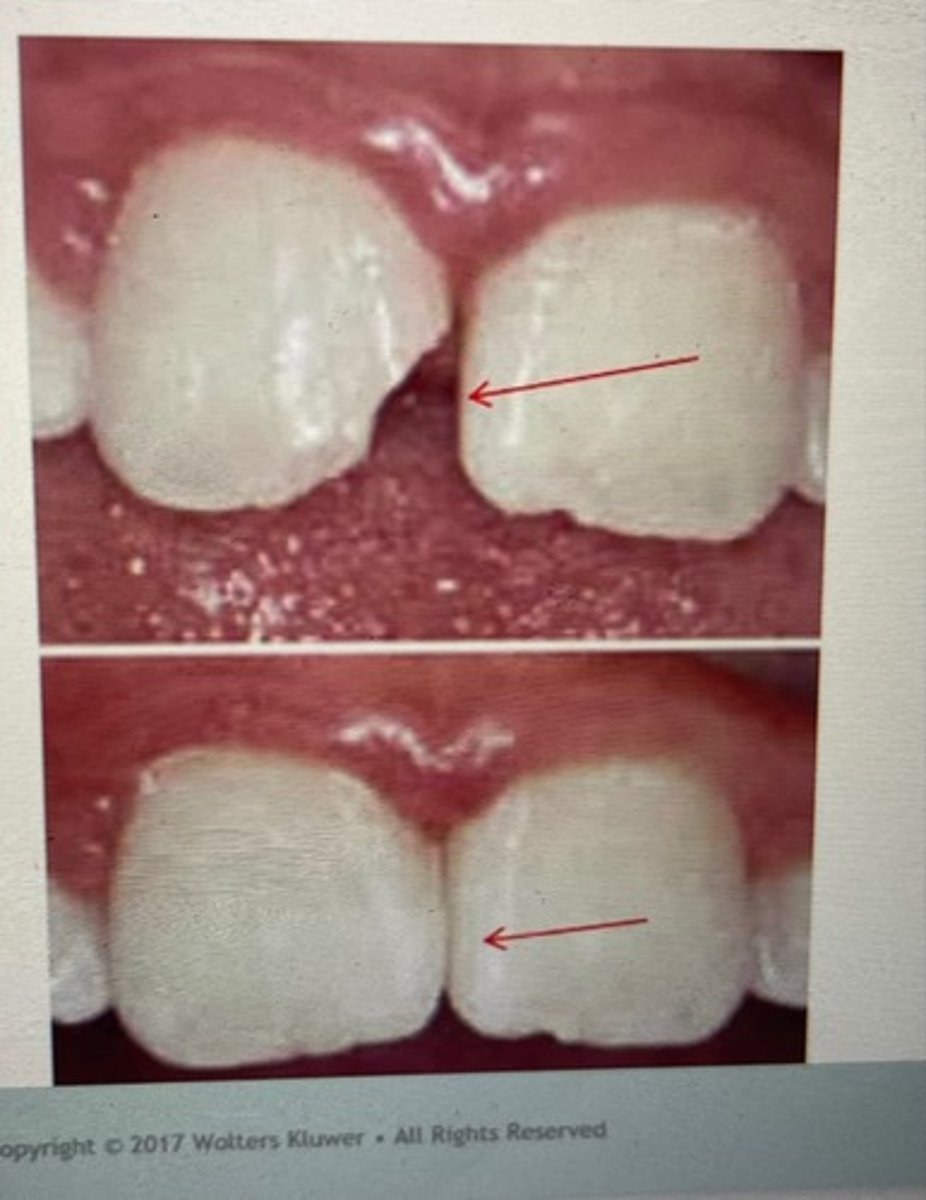

class III restoration

class IV restoration